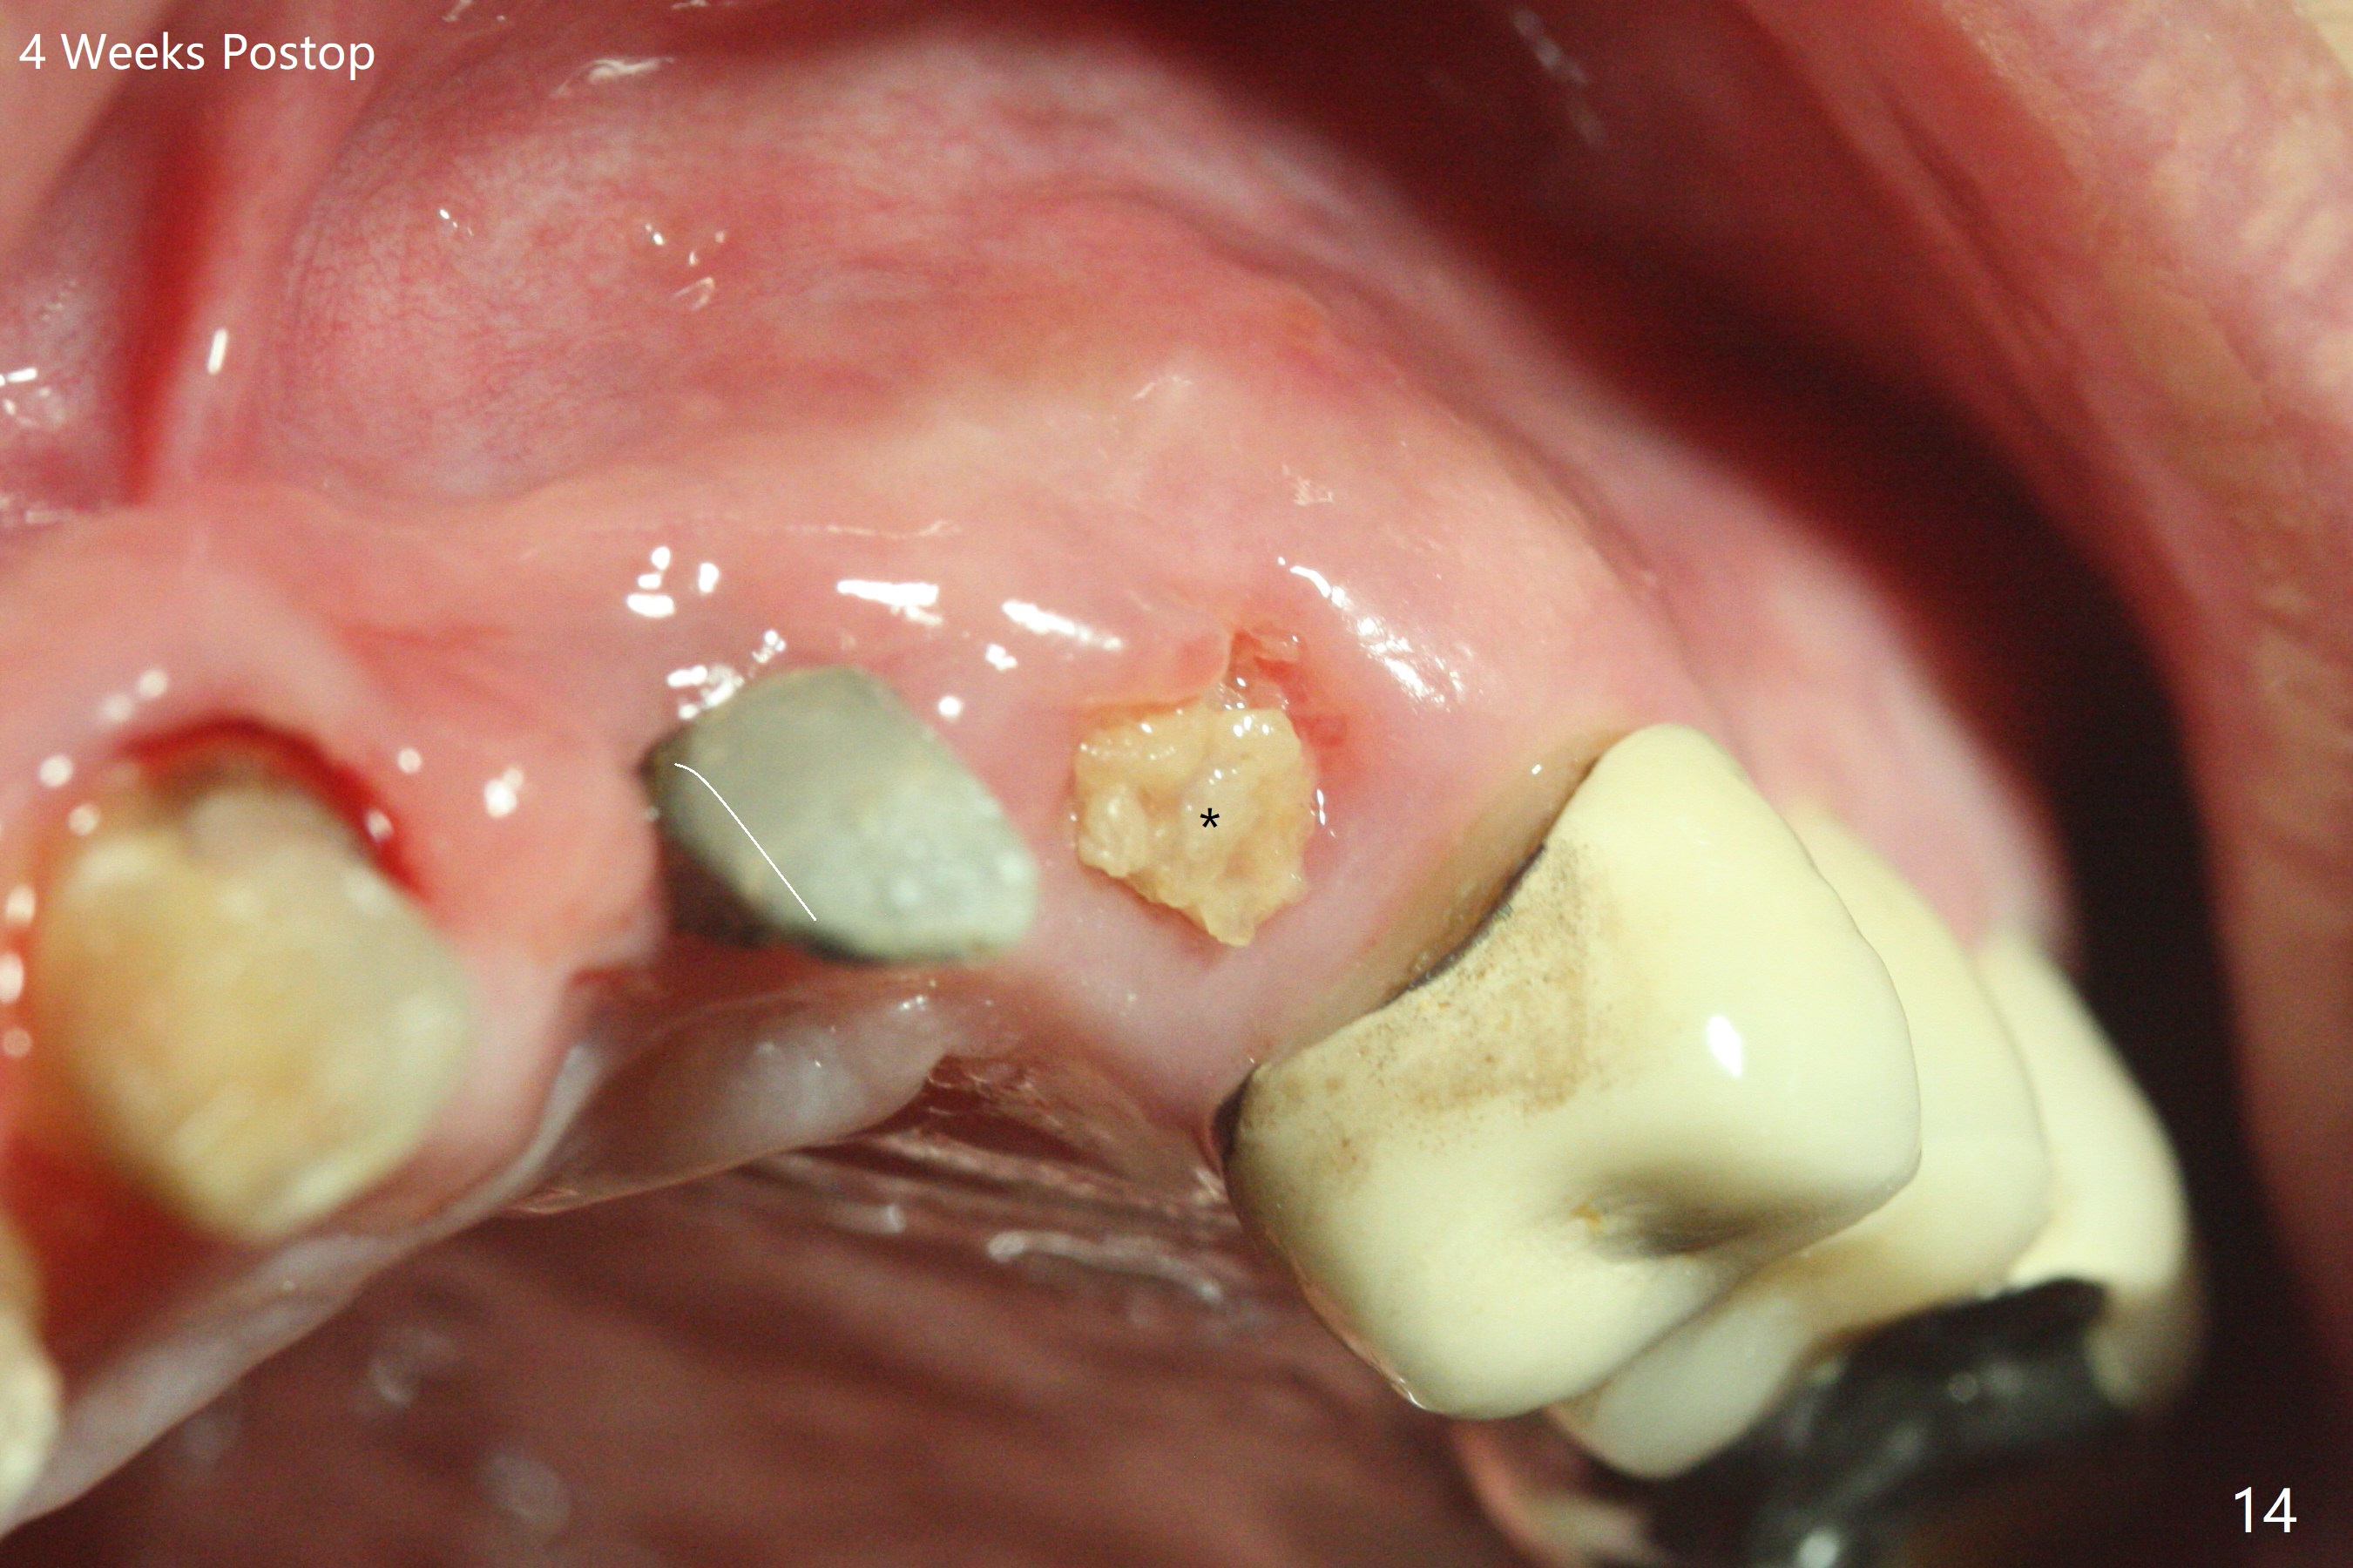

The mesiobuccal margin at #8 is redefined 4 weeks postop (Fig.14) so that the cervical end of the temporary crown is able to move mesially (Fig.13). The most coronal portion of the bone graft at #11 begins to be detached (*). The mesial portion of the abutment at #10 will be removed (curved white line) in the following week. After removing the most coronal portion of detaching bone graft at #11, acrylic is added to form a concave pontic (Fig.15 ^). With removal of the mesial portion of the abutment at #10, the retainer is moved distal (>). Pontics form at UL1 and 3 two months postop (Fig.16 *), while there is buccal atrophy at UL1,2 (Fig.17). 术后3个月植牙区牙龈形态良好(图十八),即将暴露,放置愈合基台。图十九是在右上1根管治疗时(基台放置后五天)拍摄。左上3术后3个月3个星期,1,2唇侧塌陷(图二十)。叶状植体处牙槽嵴往根尖萎缩(图二十一:^)。尽管做了松弛切口,放入事先预备的粘性骨粉后,几乎没有空间放置结缔组织移植物,恰好还没有取。放置PRF膜后,使用4-0 Monoglyc缝线缝合。牙龈似乎冠方移位(图二十二:箭头)。植骨后,唇侧仿佛饱满多了(图二十三:*)。骨粉放置于左上1,2唇侧和牙槽嵴(图二十四:*,与之前(图十九)对比)。后者有助于牙龈冠方移位,而前者有助于增加唇侧饱满度。植骨术后两周唇侧仍饱满(图二十五,六)。植骨后四个月牙冠粘固,两个月后,病人抱怨10号牙左右食物坎塞(图二十七),9/10牙冠撤除,10基台边缘加深,重做临时牙冠,同时增加9凹陷(pontic)。一个月后,9/10临时牙冠修整两次,11永久性牙冠撤除,也制备临时牙冠,外形明显改善(图二十八)。